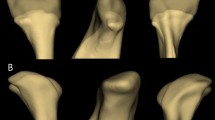

Twenty-six patients with 34 joints were included in the study (Table 1). They all had disc displacement without reduction by MRI examination (Fig. 1). Among them, there were 14 males and 12 females, with an age ranged from 4 to 49 years old (mean, 32.6 years). One patient with bilateral ATDD without Reduction also had a combined mandibular symphysis fracture which was reduced and rigid fixed immediately after injury. But his bilateral ATDD developed to osteoarthritis after 6 months conservative treatment. Four patients had one joint of ATDD, and the other joint of ICF. One of the 4 ICFs developed to ankylosis after 4 months conservative treatment and accepted costochondral graft for joint replacement. The other 3 ICFs healed with malunion of the ramus. The follow-up period was from 3 to 24 months (mean, 8.69 months).

At the end of conservative follow up, MRI showed condylar bone intact in 6 patients with 8 joints (23.5%), condylar surface bone destruction (Wilks IV, V stages) in 13 patients with 14 joints (41.2%, Fig. 2), and severe bone resorption in 7 patients with 12 joints (35.3%, Fig. 3, Table 1).